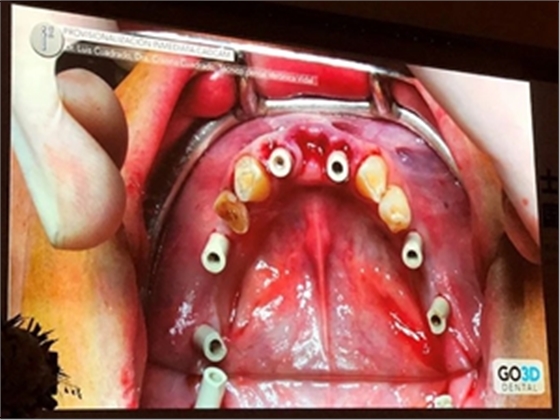

在Dr. Luis Cuadrado的全數(shù)字化修復(fù)流程中,因不需取傳統(tǒng)模型而更為高效精準(zhǔn)。Dr. Luis Cuadrado通過(guò)病例展示了他的標(biāo)準(zhǔn)步驟:

第一,使用口掃設(shè)備對(duì)患者掃描,制取數(shù)字化研究模型。

第二,拔除余留牙。Dr. Luis Cuadrado建議此時(shí)保留至少兩顆患者天然牙以作為掃描參考點(diǎn)。

第三,植入種植體,安裝掃描桿,并再次進(jìn)行口內(nèi)掃描,獲取數(shù)字化植入信息。

第四,技工中心可以籍由植入前后天然牙為參考點(diǎn),在軟件上將兩次數(shù)字化印模進(jìn)行精準(zhǔn)結(jié)合,從而制作與患者術(shù)前咬合關(guān)系一致的臨時(shí)義齒。

接下來(lái),Dr. Luis Cuadrado將全數(shù)字化修復(fù)流程同CT導(dǎo)板引導(dǎo)種植流程相結(jié)合,實(shí)現(xiàn)術(shù)前即可在軟件上制作數(shù)字化修復(fù)體。通過(guò)在計(jì)算機(jī)設(shè)計(jì)時(shí)將基臺(tái)數(shù)據(jù)(角度、高度信息等)信息轉(zhuǎn)移到導(dǎo)板上,使植入后修復(fù)更符合美學(xué)、功能等標(biāo)準(zhǔn)。